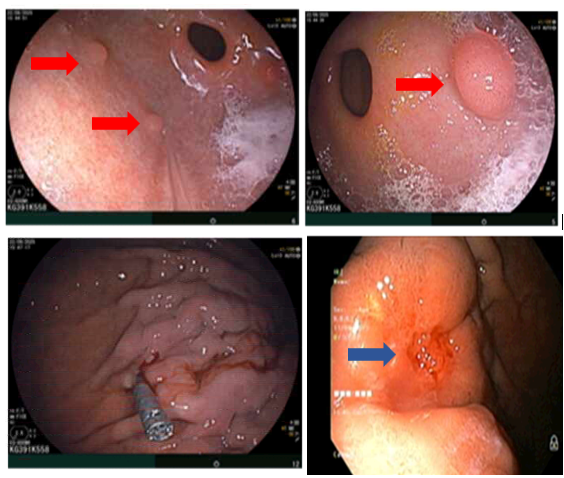

– Nội soi dạ dày: Thân phình vị, thân vị có đám niêm mạc co kéo, hội tụ, lõm ở trung tâm kích thước ~ 3.0cm, bề mặt niêm mạc biến đổi

Hình 2. Hình ảnh các polyp ở dạ dày (mũi tên đỏ). Niêm mạc dạ dày co kéo, lõm ở trung tâm (mũi tên xanh)

– Nội soi đại tràng: Phần quan sát được: Dọc đại tràng có nhiều polyp, tập trung ở đại tràng sigma kích thước ~ 0.3- 0.6 cm. Trực tràng có nhiều polyp kích thước ~ 03-0.6 cm.

Hình 3. Hình ảnh các polyp rải rác ở đại tràng (mũi tên đỏ)